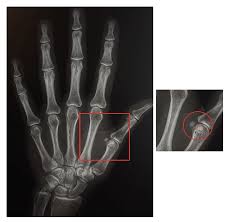

Flexor tendon injuries of the hand involving zone ii. The fds and fdp tendons should be tested individually; Jersey finger (rugby finger) is an avulsion of the flexor digitorum profundus tendon (fdp) from its distal insertion on the distal phalanx (zone i). In these cases, the tendon is often cut into two pieces. Since the ring finger protrudes the farthest in the grasping position, it is more susceptible to fdp avulsion causing an inability to flex at the dipj. A pressure mapping sensor placed under the fingertip measured the contact force and area in response to fdp tendon loading for the intact tendon and 3 repair sites along the fdp footprint. Flexor digitorum superficialis (fds) instruct the patient bend your finger at the middle joint while stabilizing their other fingers (otherwise fdp tries to help out) insertion: They were divided into test and control groups (20 patients each). Please do not remove this. Fds / fdp flexor tendon repair dr. Together the flexor pollicis longus, pronator quadratus, and flexor digitorum profundus form the deep layer of ventral forearm muscles. Test for flexor carpi ulnaris (fcu) tendon. The wrist is bent up and toward the little finger.

Jersey finger (rugby finger) is an avulsion of the flexor digitorum profundus tendon (fdp) from its distal insertion on the distal phalanx (zone i) fdp tendon. Because flexor tendons are very close to the surface of the skin, a deep cut will most likely hit a flexor tendon.